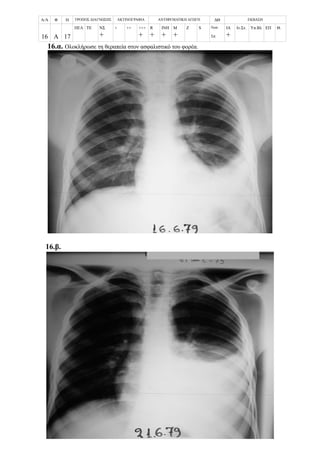

Περίπτωση 16η:

Α/Α Φ Η ΤΡΟΠΟΣ ΔΙΑΓΝΩΣΗΣ ΑΚΤΙΝΟΓΡΑΦΙΑ ΑΝΤΙΦΥΜΑΤΙΚΗ ΑΓΩΓΗ ΔΘ ΕΚΒΑΣΗ

16 Θ 10

ΠΕΛ ΤΕ ΝΣ

+

+ ++ +++

R

ΙΝΗ

Μ

Z S Νοσ.

Σπ.12

ΙΑ

Ιν.Στ. Υπ.Βλ ΕΠ Θ.

16.α. Επαφή

16.β.

3/3/1987

10-03-87

16.γ.

16.δ.

10/3/1987

18/5/1987

16.ε.

16.στ.

25/8/1987

9/6/1988